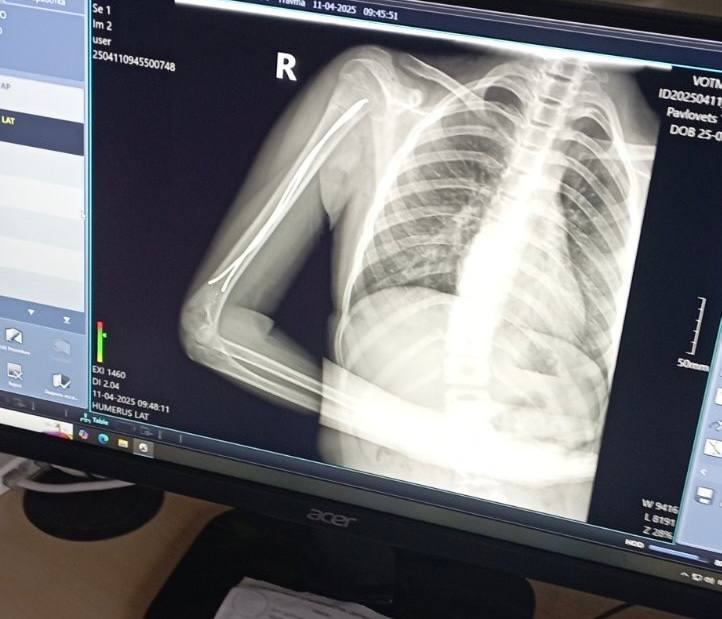

Дворічний Даніель отримав важку травму вдома – бігав, упав. Як наслідок – косий перелом стегнової кістки, складний для вправлення та лікування, утримання відламків.Ортопед-траматолог Ігор Тарасюк пояснює: «Лікування гіпсовими пов’язками хлопчику не підходить, тож раніше діти з такими травмами лікувалися впродовж місяця на витяжінні, а після цього застосовували кокситну гіпсову пов’язку, яка утруднювала рухи. Завдяки внутрішньокістковій фіксації еластичними титановими стержнями дитину виписуємо додому вже наступного дня. Хлопчик, хоч і з певними обмеженнями, але вже може самостійно рухатися».Ще одна пацієнтка відділення — 11-річна футболістка Юля, яка невдало впала на плече під час гри. Як наслідок – перелом плечової кістки зі зміщенням. Раніше через такий перелом довелося б носити велику гіпсову пов’язку на руці – від кисті до плеча, також гіпс накладали б для фіксації і на обидва плеча.Після операції через два-три дні дівчинка вже вільно рухає рукою, не відчуває обмежень. На руці залишиться лише невеликий шрам у 2-3 сантиметри. Через кілька тижнів дівчинка зможе повернутися до занять футболом.Читати ще: Арахіс у легенях, магніти в стравоході та опіки від побутової хімії: волинські лікарі розповіли, із чим до них привозять маленьких пацієнтів